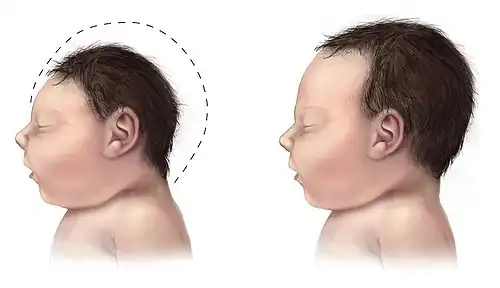

Dyggve-Melchior-Clausen (DMC) Syndrome is a rare autosomal recessive disorder that stunts skeletal and intellectual development.[1] Individuals with this disorder often present with a shorter stature, minimal or decreased joint mobility, deformities of the spine, and microcephaly.[2] Individuals with this disorder exhibit varying degrees of intellectual disability, with some individuals being impacted more severely than others.[1][2]

The first symptoms appear in newborns, which are slightly shorter in body length.[3] Symptoms are progressively more noticeable as a child ages, with more skeletal deformities presenting before 18 months of age.[3] Abnormal skeletal development can present as progressive dwarfism, a barrel-shaped chest, rhizomelic limb shortening, dolichocephaly, microcephaly, coarse facial features, spondyloepiphyseal dysplasia, genu valgum, genu varum, and prognathism.[1][2][3][7] In addition to skeletal changes, individuals affected by DMC syndrome will present with a range of intellectual disabilities.[3]